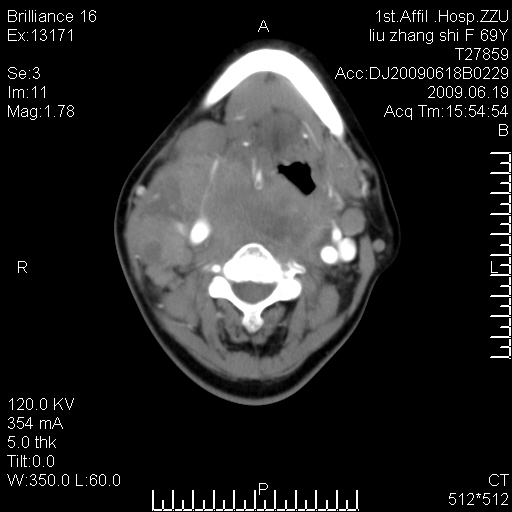

标题: CT26782:女,69岁,颈部占位,3天后公布病理结果。

【病理证实系列】女,69岁,颈部占位,有病理结果,3天后公布。(由于病例时间较久,临床资料不全,请网友见谅)本系列将有几百种常见、少见及罕见病例,均经病理证实。病例资料来自郑州大学第一附属医院。与网友共享,本人有空就发。

甲状腺癌并颈部淋巴结转移。感谢楼主的良苦用心,谢谢。

甲状腺癌并颈部淋巴结转移。

需与鼻咽癌鉴别!

支持甲状腺癌广泛侵及周围结构并颈部淋巴结转移。

鉴别:淋巴瘤、恶性神经源性病变、恶性纤维组织细胞瘤。

病理结果:颈部非霍奇金淋巴瘤。